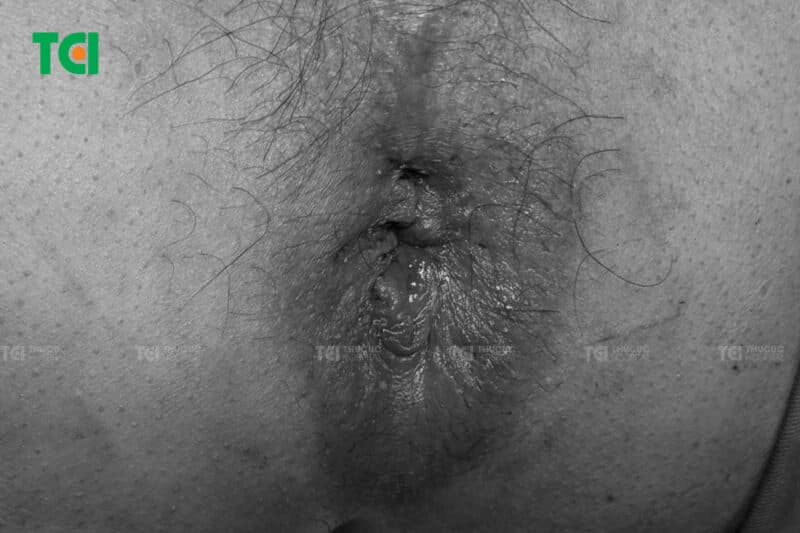

3.2. Dấu hiệu bệnh trĩ ngoại

Khác với trĩ nội, trĩ ngoại hình thành bên ngoài hậu môn, có thể nhìn thấy bằng mắt thường. Bệnh nhân thường cảm nhận được khối sưng đau quanh hậu môn, đặc biệt khi ngồi lâu hoặc vận động mạnh. Ngoài ra, người mắc trĩ ngoại còn có hiện tượng đau rát, tiết dịch, ngứa ngáy và có thể chảy máu khi búi trĩ bị tổn thương.